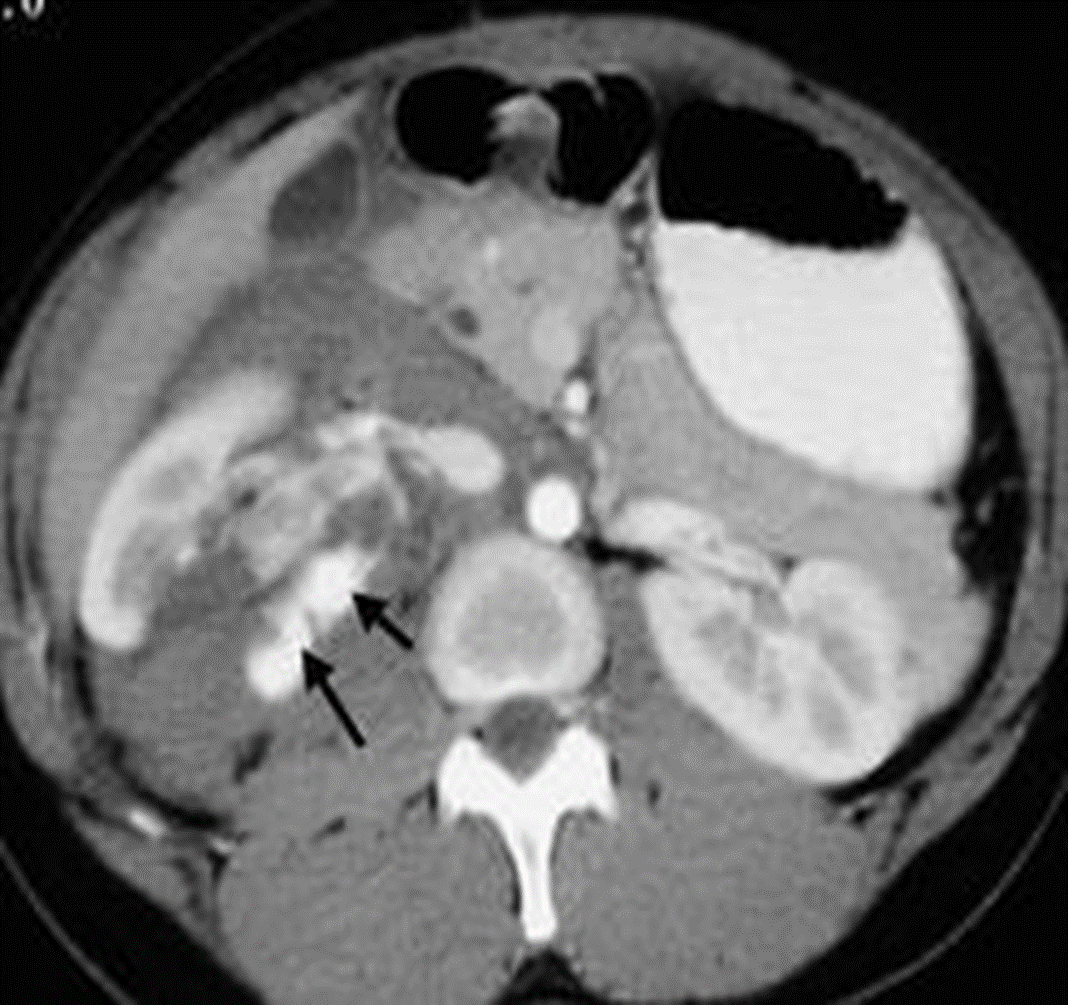

Young male patient involved in a motor vehicle accident with blunt trauma to the abdomen.

CT show ruptured RT kidney